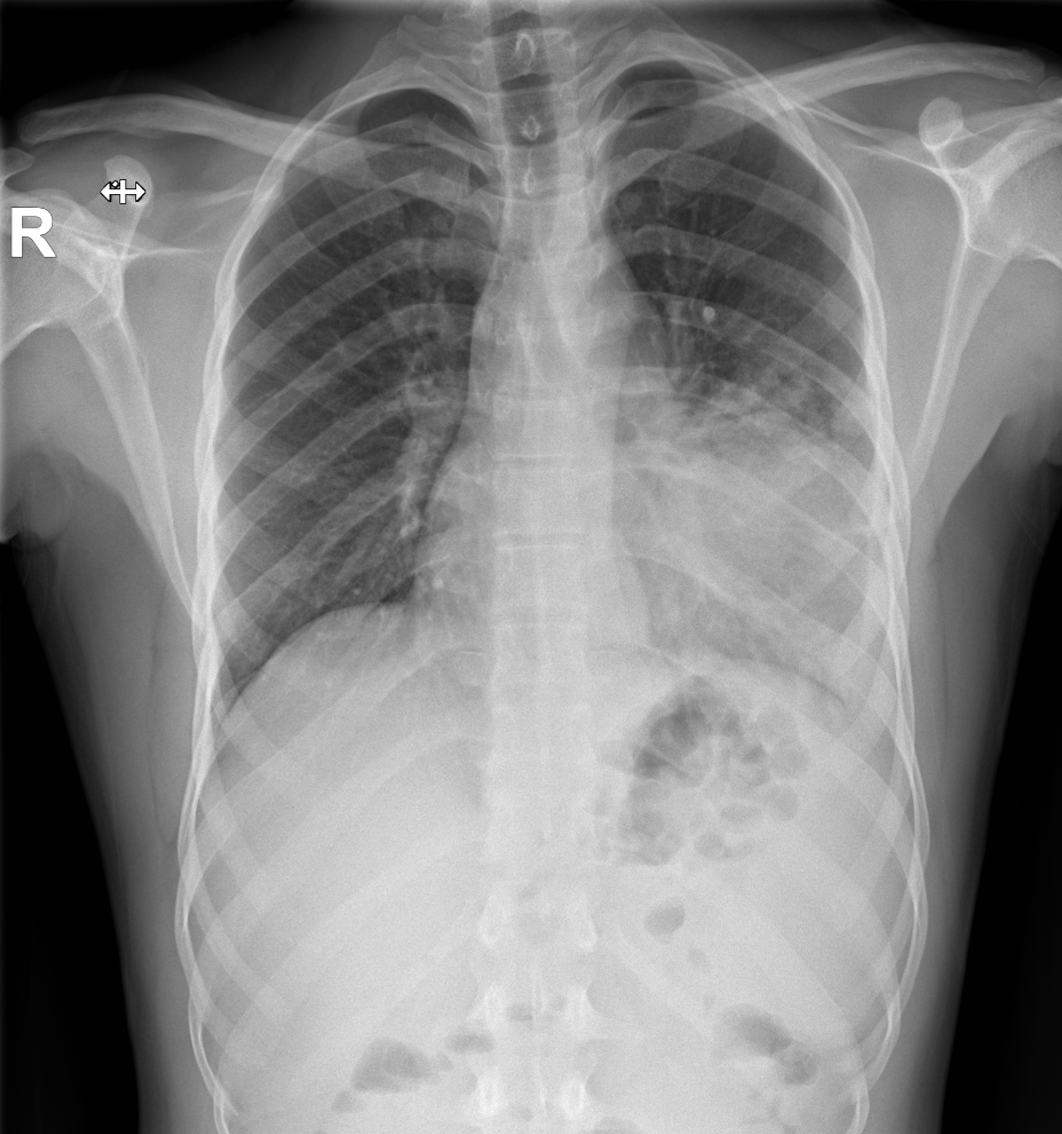

Exploración: buen estado general, eupneico, afebril, constantes vitales estables. Saturación de oxígeno 100%. Sin trabajo respiratorio. Auscultación pulmonar objetiva hipofonesis en lóbulo inferior izquierdo (LII) y crepitantes dispersos. No edemas.

Consolidación en LII y derrame pleural izquierdo a estudio.

Ingreso en Neumología, donde realizan toracocentesis y bioquímica líquido pleural, con evidencia de exudado mononuclear y ADA 80 U/L. Se realiza PCR líquido pleural positivo para M. tuberculosis. Antigenuria, hemocultivo y serología de virus negativos. Cultivo de esputo no representativo. Se diagnostica de tuberculosis pleuropulmonar izquierda e inician tratamiento antituberculoso con controles radiológicos posteriores.

La tuberculosis pleural es una forma frecuente de tuberculosis extrapulmonar, manifestada como derrame pleural aislado o asociando lesiones pulmonares (tuberculosis pleuropulmonar). Su diagnóstico requiere demostrar M. tuberculosis en líquido o biopsia pleural, aunque ADA e interferón gamma ofrecen alta sensibilidad y especificidad clínica. Además de la clínica y radiografía torácica, la ecografía aporta ventajas en Urgencias, permitiendo detectar derrame o engrosamiento pleural y septaciones, así como guiar procedimientos invasivos y monitorizar manejo y evolución clínica.